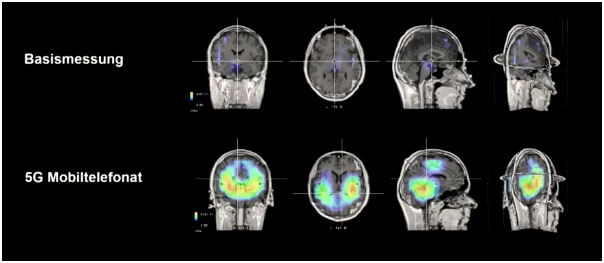

Das gut einstündige Interview mit den beiden Forschern zeigt so manche neue Erkenntnis, die erschreckend ist. Verdeutlicht werden die Aussagen anhand von neuartigen 3D-EEG-Aufnahmen, auf denen erstmals auch für Laien ersichtlich wird, wie tief (räumlich gesehen) die Strahlungen ins Gehirn eindringen und dadurch auch Schäden auf Mitochondrienebene stattfinden können und auch der Hypothalamus betroffen ist.